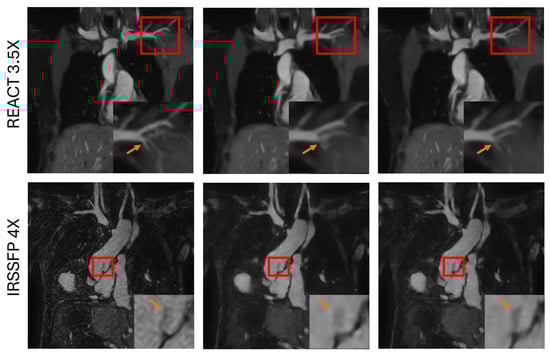

2. Materials and Methods

3.4. Evaluation of the Robustness of the Proposed Framework